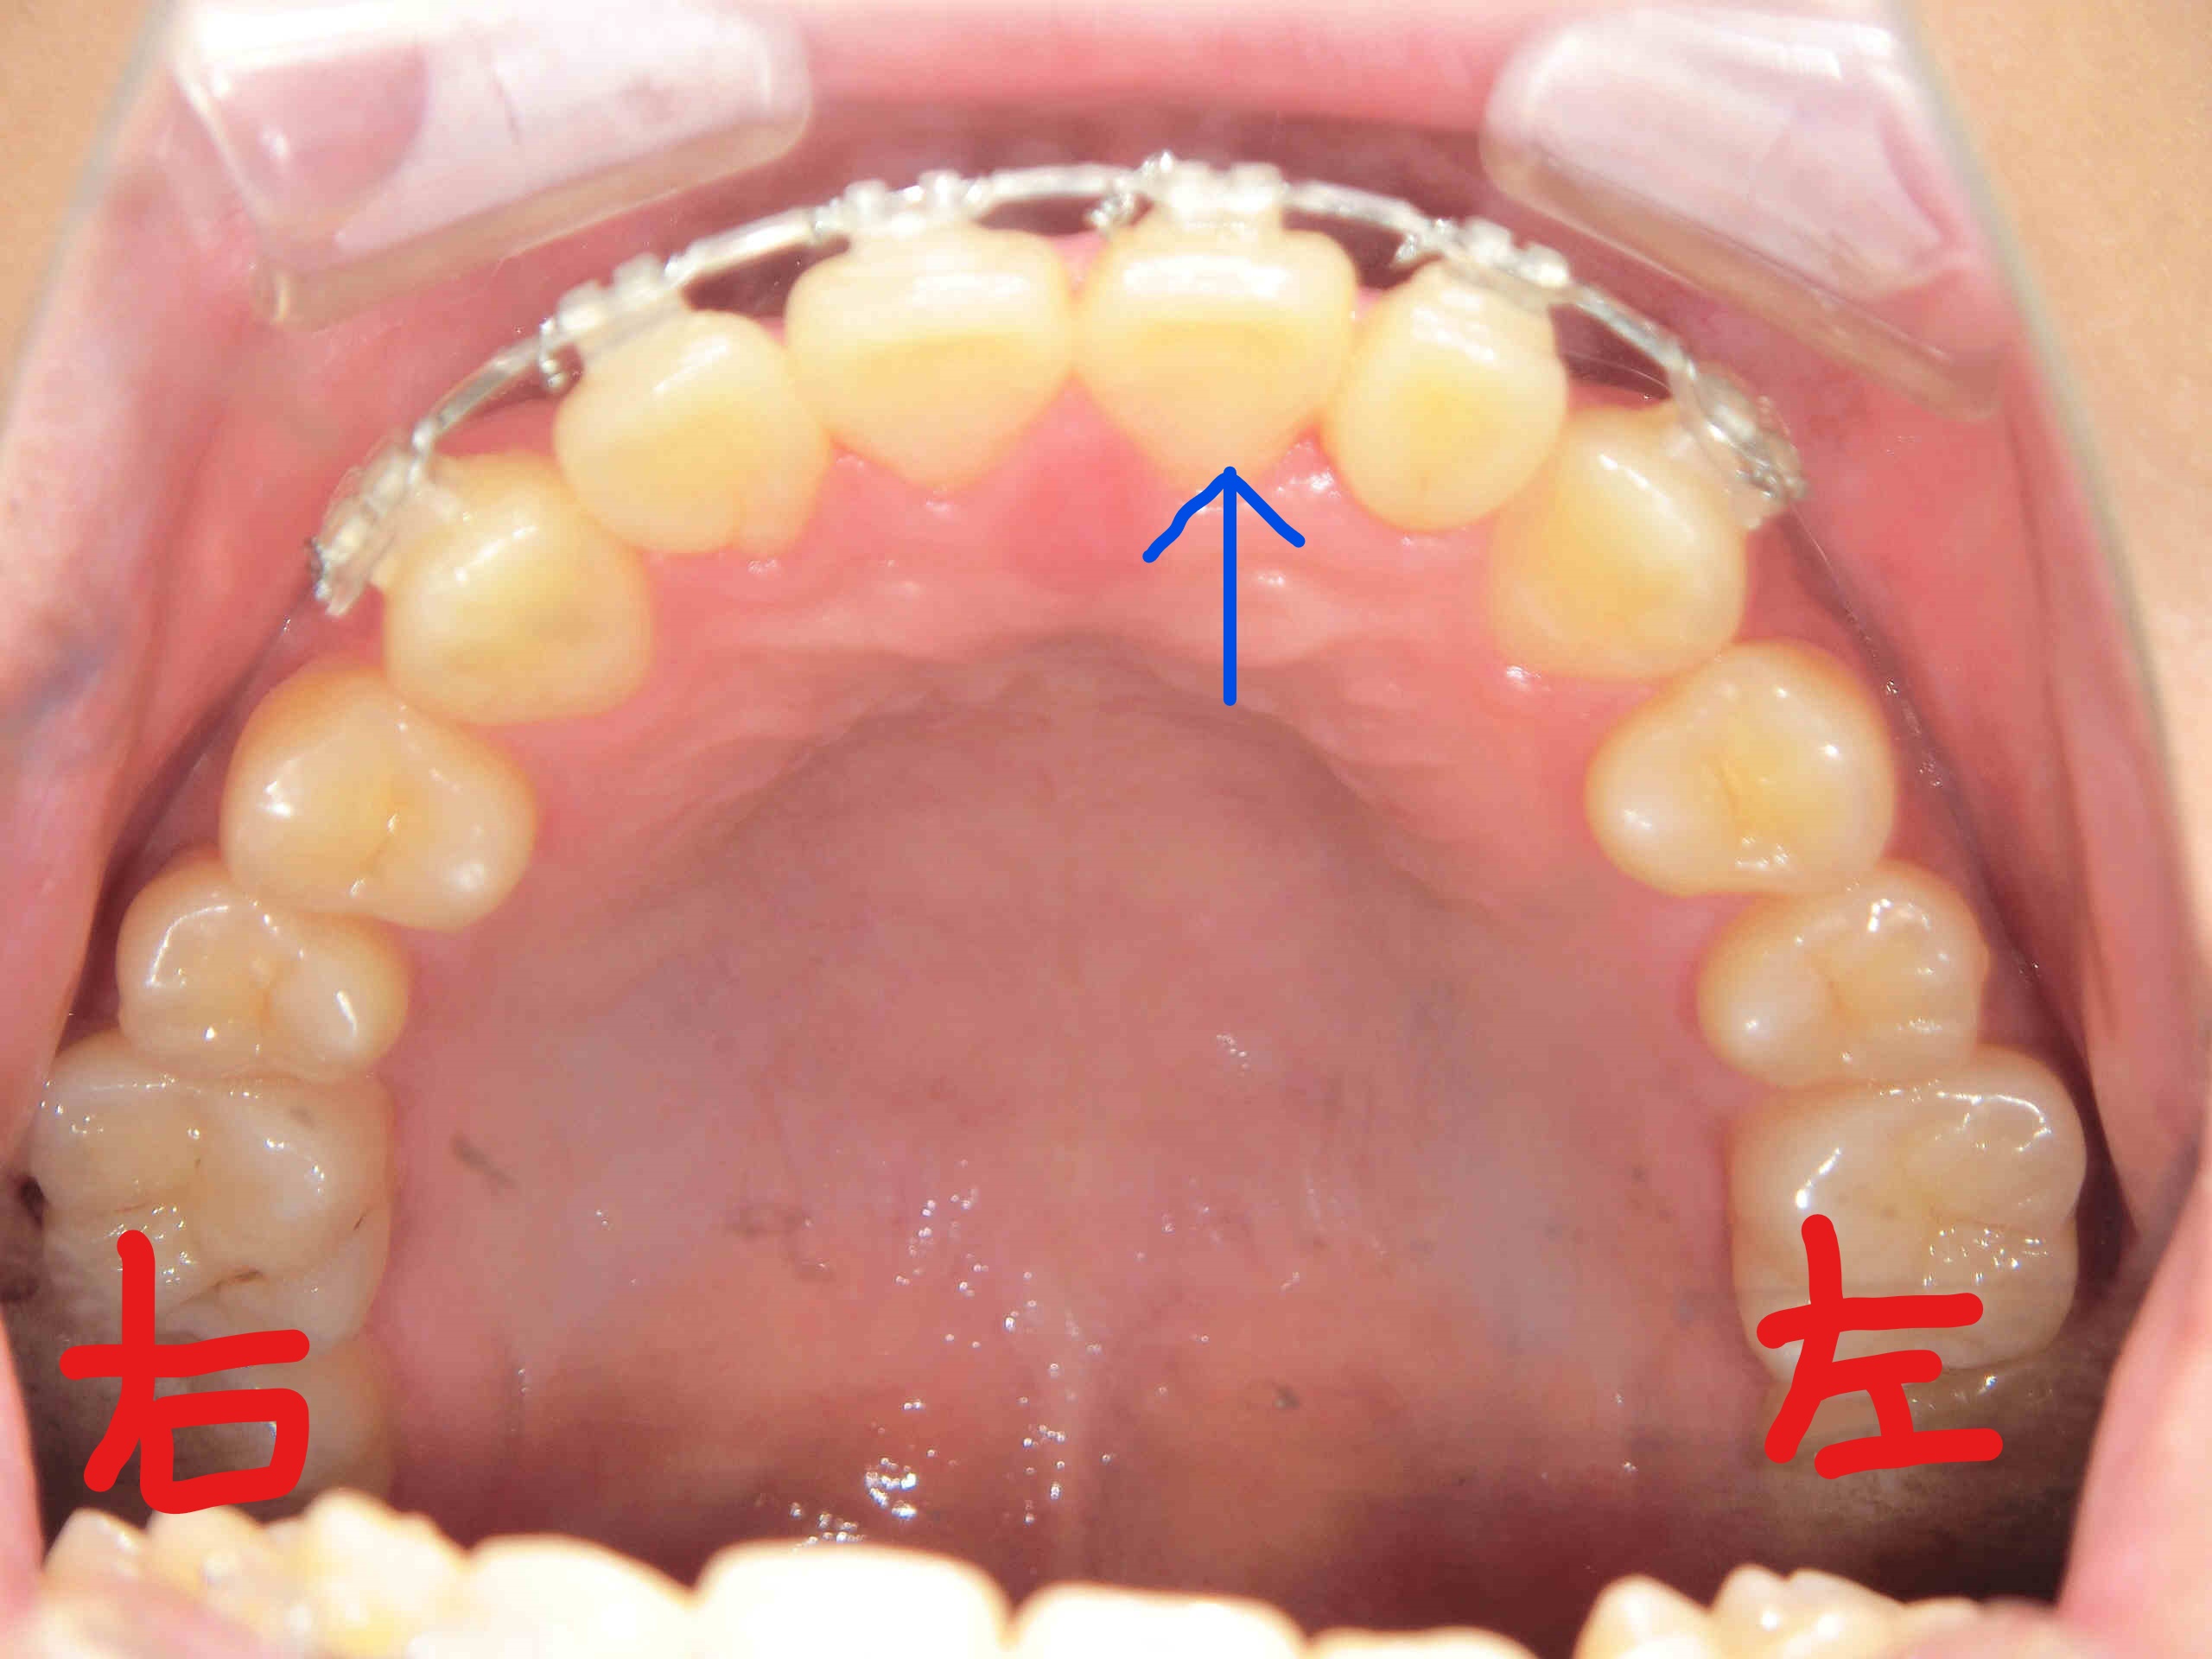

次に、左上がブラケットを撤去する直前の上顎を下から見上げた写真、右上がブラケット撤去直後の写真です。青色矢印の歯にご注目ください。左上の前歯の捻転がしっかりと改善されているのがお分かりいただけると思います。

治療期間は2週間に一度ご来院いただき、わずか6 か月で完了しました。上下全顎にブラケットを装着して並べていく一般的な全顎矯正とは異なり、前歯のみを対象とした部分矯正だからこそ実現できたスピードです。患者様からも「こんなに早く終わるとは思わなかった」と驚きの声をいただきました。

治療期間:6 か月/来院回数:12回/治療費:調整料を含めて221,880円(税込)